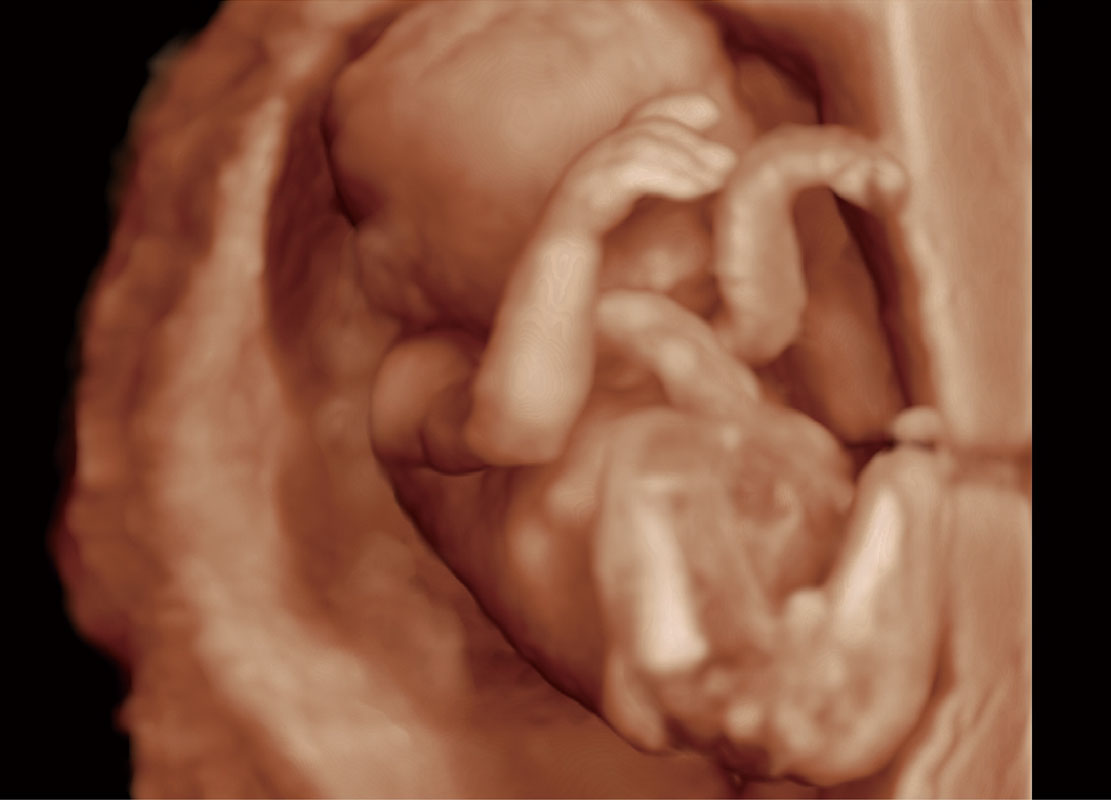

高分辨率容积成像-早孕胎儿

P60提供简单易学易用的高端诊断工具,为您中晚孕筛查提供快速清晰的解剖信息。